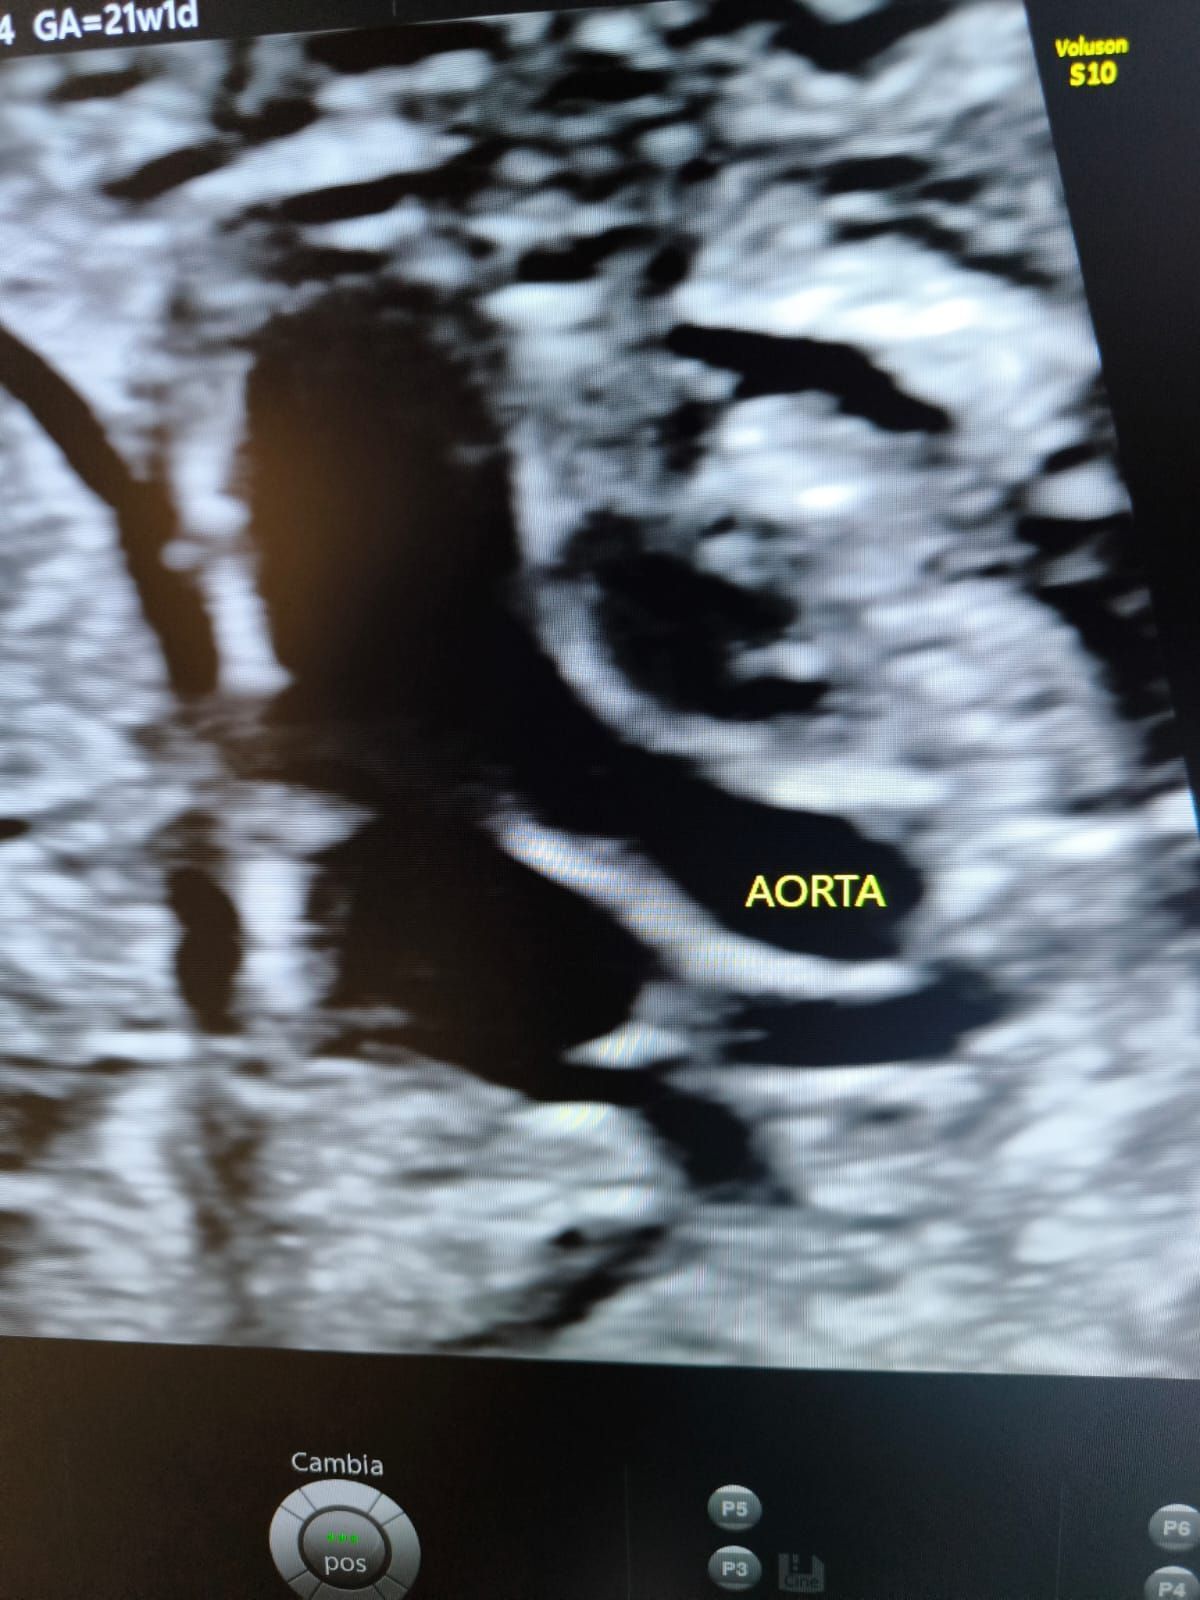

- Ecocardiografia Fetale;

- Doppler-Flussimetria;